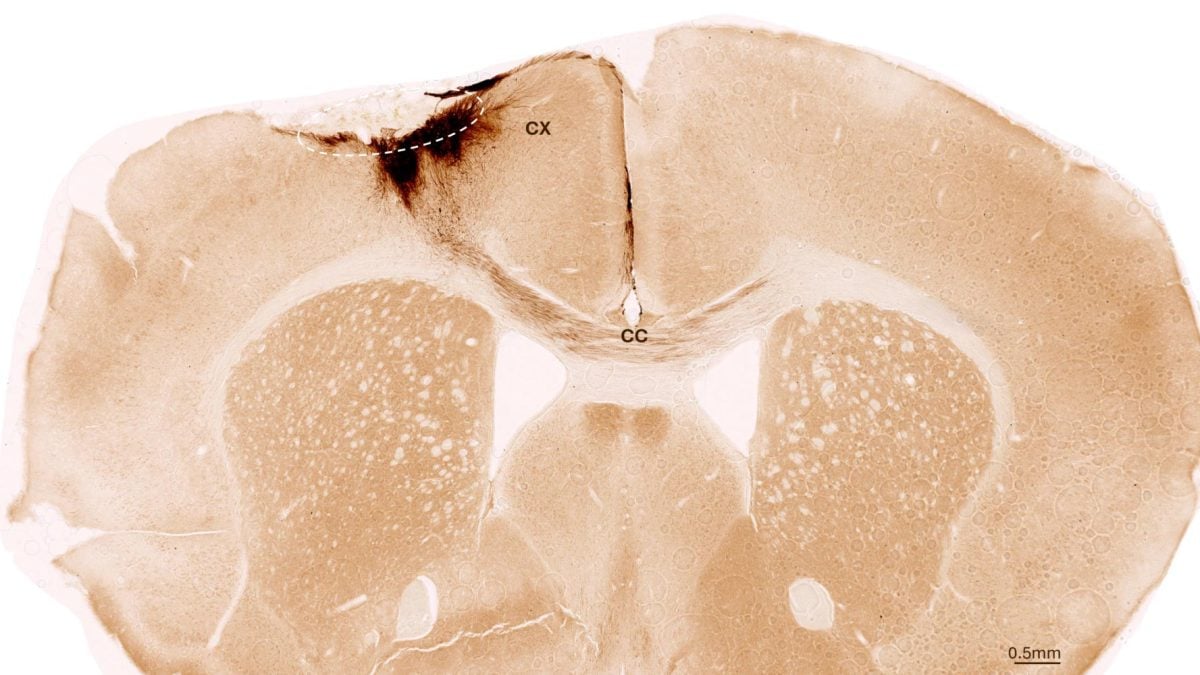

Hình ảnh này chụp cắt lớp não chuột sau đột quỵ và ghép tế bào gốc thần kinh, với vòng tròn nét đứt đánh dấu vùng bị đột quỵ, trong khi các nhánh thần kinh được tạo ra từ tế bào gốc của người được tô màu nâu sẫm - Ảnh: ĐẠI HỌC ZURICH

Nhóm nghiên cứu đã thí nghiệm những con chuột bị đột quỵ và được biến đổi gene để không đào thải tế bào của con người.

Một tuần sau cơn đột quỵ, những con vật này được ghép tế bào gốc thần kinh của người, là loại tế bào có thể biến đổi thành các loại tế bào khác nhau của hệ thần kinh.

"Chúng tôi phát hiện ra rằng các tế bào gốc sống sót trong suốt thời gian phân tích kéo dài 5 tuần và hầu hết chúng đã chuyển hóa thành tế bào thần kinh, thậm chí còn giao tiếp với các tế bào não đã tồn tại" - đồng tác giả Christian Tackenberg từ Đại học Zurich nói với SciTech Daily.

Sự tái tạo não bộ mà liệu pháp này mang lại cho những con chuột bị đột quỵ đã vượt ra ngoài tế bào thần kinh: Các tác giả còn quan sát thấy sự hình thành mạch máu mới, giảm viêm và cải thiện tính toàn vẹn của hàng rào máu não.